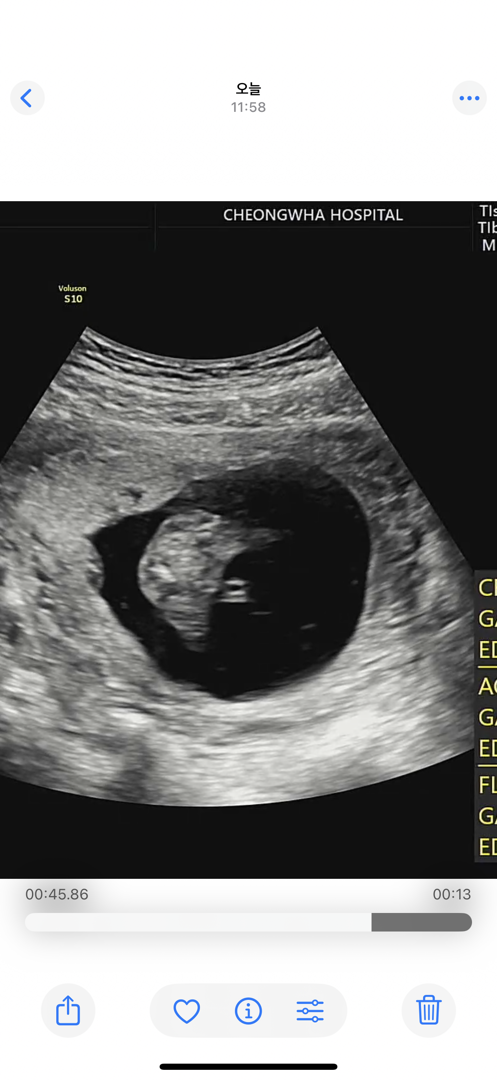

16주 성별 ㅠㅠ

사진이 하나밖에 안올라가네요..! 이 화면에 멈춰서 이건 탯줄이고 이건 아기 피부인데 아들이면 그것이 있겠죠? 라고 하셨는데 공주님 맞나요…? 원장님 말로만 하면 튀어나온건 탯줄뿐인데..

딸같아용

딸같아요~~